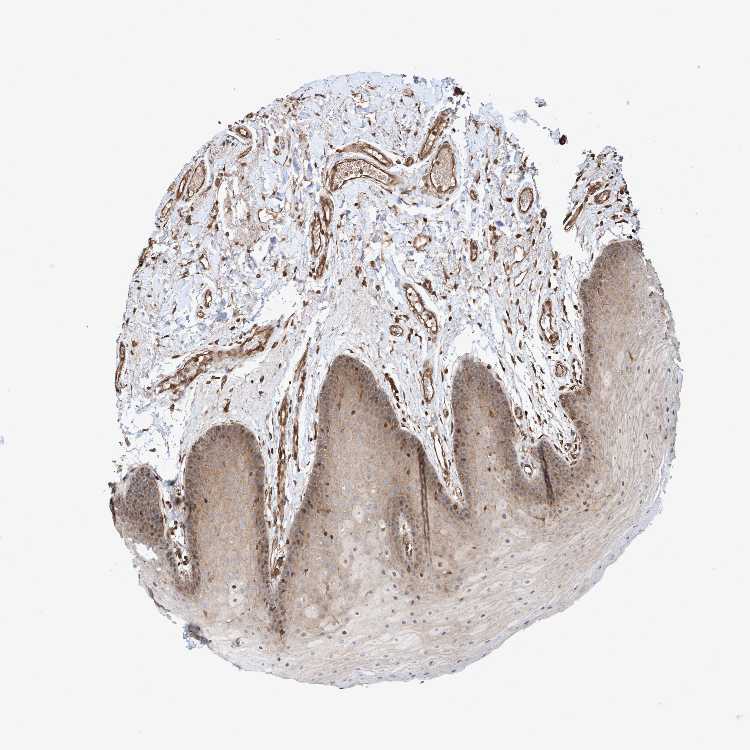

TISSUE PRIMARY DATA ORAL MUCOSA Show tissue menu

Oral mucosa

ORAL MUCOSA - Antibody stainingi

Antibody staining in the annotated cell types in the current human tissue is reported as not detected, low, medium, or high, based on conventional immunohistochemistry profiling in selected tissues. This score is based on the combination of the staining intensity and fraction of stained cells.

Each image is clickable and will lead to virtual microscopy that enables deeper exploration of all samples and also displays staining intensity scores, fraction scores and subcellular localization as well as patient and tissue information for each sample.

Antibody HPA021425Antibody HPA024423

Squamous epithelial cells MediumMedium